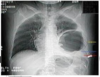

Diagnóstico?

Hérnia diafragmática